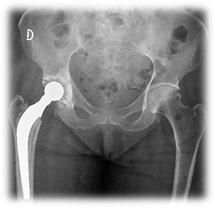

- Artroplastía

Parcial o total de cadera (Figura 4)

Paciente en decúbito contralateral al lado a operar. Se realiza abordaje posterolateral (Gibson). Fasciotomía, bursectomía, se identifican pelvirrotadores y se los secciona con electrobisturí. Capsulotomía en L o T. Se extrae la cabeza femoral. Se regulariza fractura, basicervical, con gubia. En un primer tiempo, si es un RTC, se trabaja el componente acetabular, con fresas crecientes, se prueba y se coloca componente definitivo (previo cementado para pacientes añosos). En un segundo tiempo o en el caso de un RPC, se trabaja canal femoral con raspas crecientes, se prueba prótesis, colocación de tapón óseo con tejido autólogo o sintético y se cementa la prótesis definitiva. Se reduce y se comprueba estabilidad. Cierre por planos.

Figura 4- Artroplastía parcial o total de cadera

Figura 4